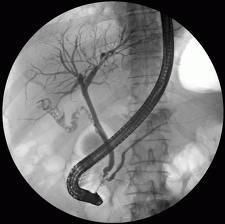

Endoskopik retrograd kolanjiopankreatografi safra ve pankreas kanallarının problemlerini tedavi etmek için üst gastrointestinal (GI) endoskopi ve x ışınları birleştiren bir işlemdir. ERCP safra ve pankreas kanallarındaki sorunları teşhis etmek için de kullanılır. Ancak non-invaziv bir yöntem olan manyetik rezonans kolanjiopankreatografi (MRCP) tanıda ERCP ‘ nin yerini almıştır1. Tanı amaçlı öncelikle MRCP yapılır. Ancak tanıyı takiben muhtemel tedaviye yönelik bir işlem gerekiyorsa ERCP önceliklidir.

ERCP işlemi gastroenterolog ve eğitim almış cerrahlar tarafından hastane veya ayaktan tedavi merkezinde yapılır. Hastaların boğazı gargara veya boğaz arkasına püskürtülen sprey ile uyuşturulur. Bu lokal anestezi sayesinde boğaz uyuşur ve hastanın öğürme refleksi yatışır. Sedatifler (sakinleştiriciler) ve verilecek diğer ilaçlar için damar yolu açılır. Sedasyon süresince hastaların hayati bulguları doktor ve diğer sağlık personeli tarafından takip edilir. Sakinleştirici ile işlemi tolere edemeyen hastalarda işlem genel anestezi altında yapılır. ERCP sırasında hastalar röntgen masasına sırtüstü veya sol yan olarak yatırılır. Ucunda video-kamera ve ışık kaynağı olan yandan görüşlü endoskop (duodenoskop) mideden geçirilerek duodenuma yerleştirilir. Video-kamera görüntüyü doktorun ve ekibin izleyebileceği bir monitöre iletir. Görüntünün rahat izlenebilmesi için mide ve onikiparmak bağırsağına endoskop yoluyla hava pompalanır. Duodenal papilla görüldüğünde ucu künt bir kateter endoskop aracılığıyla papiller açıklıktan safra kanalına yönlendirilir. Kateter papilla içinde kanala geçtikten sonra, kateterden kanal içine radyo-opak madde enjekte edilir. Kontrast madde de denilen radyo-opak madde , kanalların x ışınları ile görülmesine imkân verir. X ışınları kanallarda darlık, tıkanma, taş, tümör gibi pek çok patolojinin tanısına olanak sağlar. ERCP prosedürü süresince darlık ve tıkanmalar için değişik tedavi işlemleri uygulanabilir. Tedavi işlemleri sırasında kanalları görmek için, doktor aynı zamanda floroskopi adı verilen, x-ray video kullanır. Endoskop yoluyla kanallara yönlendirilen özel araçlar ile bloke kanallar açılabilir safra taşları çıkarılır veya kırılabilir, tümörler için stent takılabilir. Stentler safra veya pankreas kanallarındaki tıkanmış akışı açmak için kullanılan plastik veya genişleyebilen metal borulardır. Fırça sitolojisi denilen bir tür biyopsi yapılabilir. Bu teknikte endoskop yoluyla uygun bir fırça kullanılarak kanalları içindeki hücreler patolojik inceleme için alınır. Toplanan hücreler daha sonra yangı veya kanser belirtileri için mikroskop ile incelenir. Bazen, safra kesesi ameliyatı sonrası cerrahi safra kaçağı şüphesi varsa ERCP yapılır. Eğer safra yolu yaralanması saptanırsa bazı tür yaralanmalar stent veya naso-bilier sonda ile tedavi edilebilir. Laparoskopik kolesistektomi + ERCP (kombine işlem)